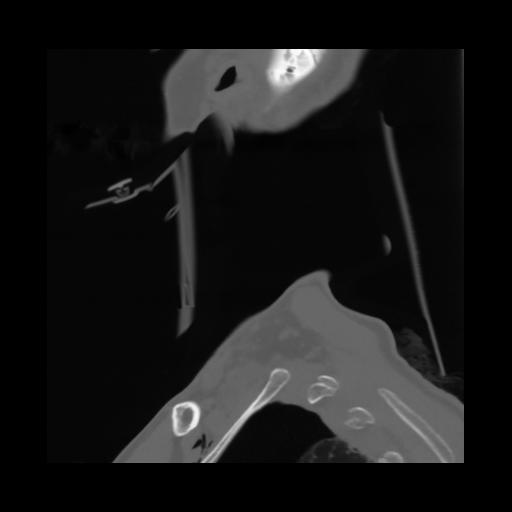

14 P.BLANDAS,,Sagittal,2.000,P.BLANDAS,Sagittal,